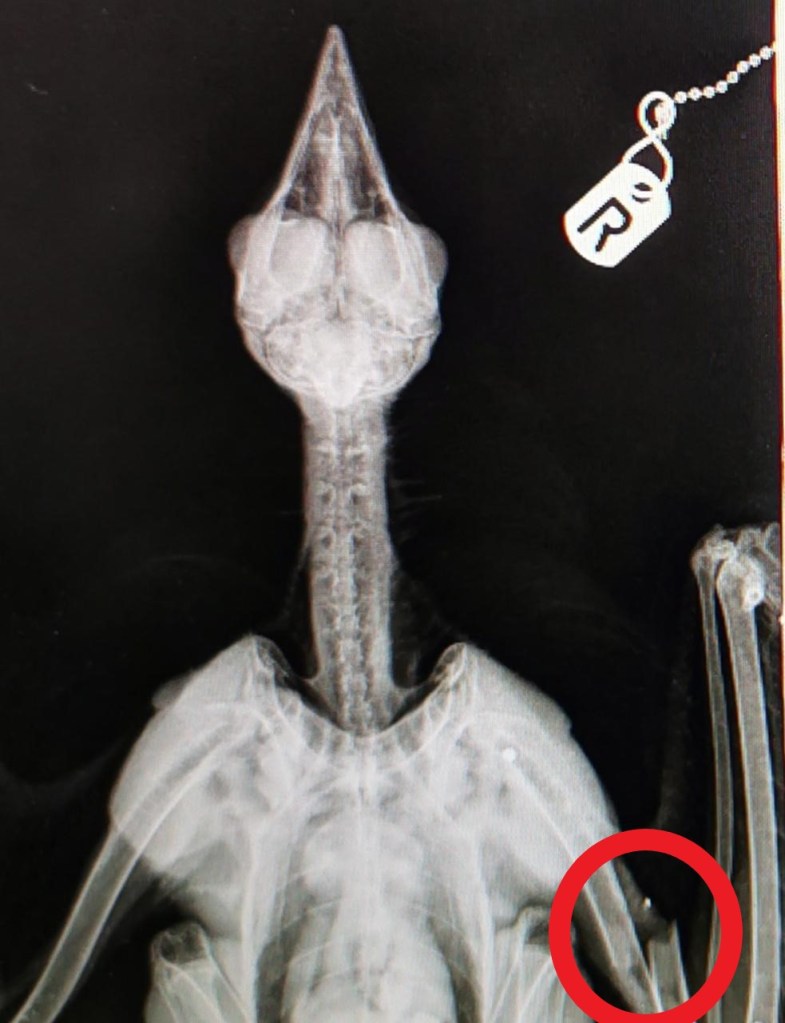

Judging by the accompanying x-ray, the kite had suffered a catastrophic wing injury and it seems unlikely it would have been able to fly far from where it had been shot (see here).

The bird was alive but unable to fly due to its severe injuries – it has suffered multiple bone fractures.

It was taken to the Vale Wildlife Hospital and, following an X-ray, it was discovered the bird had been hit with a shotgun.

It is believed it had been shot close to the village, as it would have been unable to fly or glide with its injuries. The bird had to be euthanised due to the severity of its injuries.

An X-ray of the bird revealed multiple bone fractures caused by the lead shot, therefore suggesting a shotgun was used.